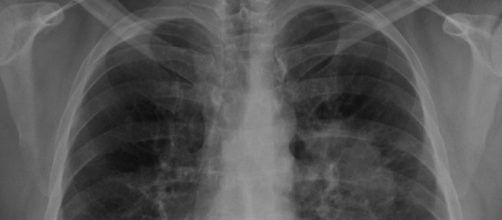

Un laboratorio clínico deberá indemnizar con unos 120.000 euros a una paciente debido a un diagnóstico médico equivocado de cáncer por lo cual a la mujer le extirparon un pulmón sin ser necesario. La Audiencia Provincial de la ciudad de Madrid ha condenado a dos médicos anatomopatólogos, junto al responsable médico del área de anatomía patológica del laboratorio por este hecho.

El laboratorio clínico indemnizará con la cantidad de 120.000 euros a la paciente a quien se le realizó una intervención quirúrgica para extirparle parte de un pulmón.

La Audiencia Provincial de Madrid ha condenado a los responsables de este diagnóstico erróneo por “negligencia médica” tras haber cometido un doble error en la evaluación de la paciente el pasado mes de abril de 2017, cuando calificaron el tumor de la mujer como “maligno y metastásico” cuando en realidad no lo era. Por este motivo, la paciente decidió demandar al laboratorio tras verse sometida a un diagnóstico equivocado de una enfermedad cancerígena que nunca ha sufrido. El laboratorio perdió la demanda ante este caso.

La paciente solicitó una segunda opinión médica con relación a su supuesta enfermedad de cáncer con las mismas muestras, las cuales fueron analizadas por el laboratorio clínico del Hospital La Paz y se terminó que el tumor no tenía características de malignidad y tampoco era metastásico.